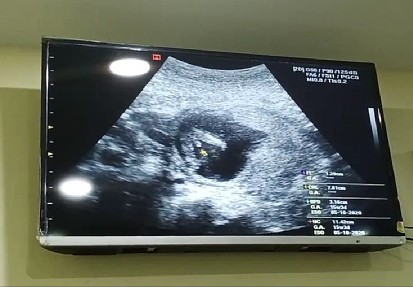

ในภาพเป็น ผช ใช่ไหมค่ะ พอดีหมอขอชัวร์ๆ เดือนหน้า เลยสอบถามแม่ๆ ที่มีประสบการณ์ลูกชาย หน่อยค่ะ ?ขอดูใบอัตตลาซาวเด็ก ผช . หน่อยจร้าาา? ถาพไม่ชัดเพราะถ่าย VDO มาจร้า ??